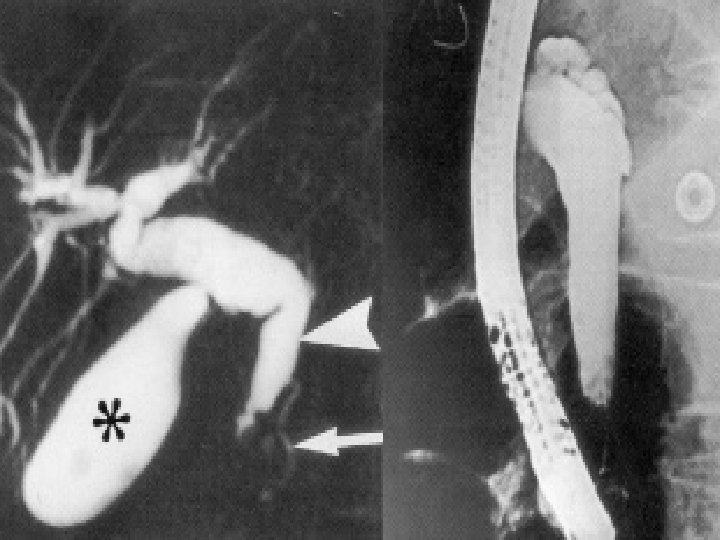

Bili IRM: Ampullome Vatérien

Ampullome avec dilatation cholédocienne

Ampullome avec dilatation du Wirsung et bourrelet duodénal